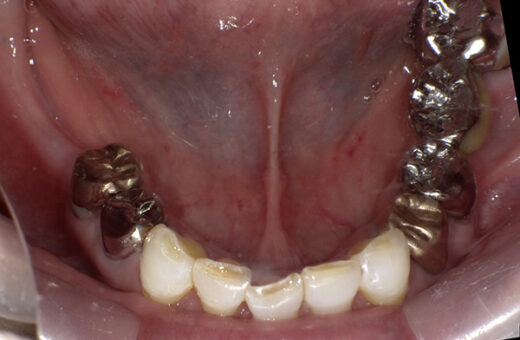

インプラント 70代(女性)

治療前

主訴

他院で作った義歯が痛くて使えない

知人がインプラント治療をして良くなったと聞いたので検討したい

症例詳細